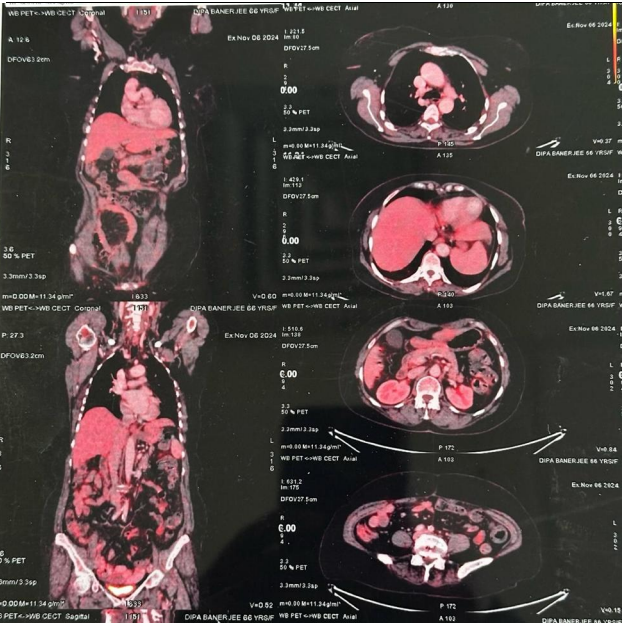

A 67-year-old female presented with abdominal pain, distension, and recurrent maliganant ascites over two months. She underwent therapeutic ascitic tapping at another hospital, draining 4 liters of fluid. PET-CT imaging revealed FDG-avid lesions in the bilateral adnexal regions, omental thickening, peritoneal deposits, and moderate ascites.

Fig 1

1. Imaging: PET-CT identified extensive metastatic involvement, including bilateral adnexal masses (largest 4.2 × 3.6 cm), peritoneal deposits, and omental caking.  [Fig.1]

First-line Therapy: The patient received six cycles of Cisplatin and Etoposide, leading to a significant response as noted on interim PET-CT scans [Fig 2]. However, disease progression was observed post-treatment.

Figure 1